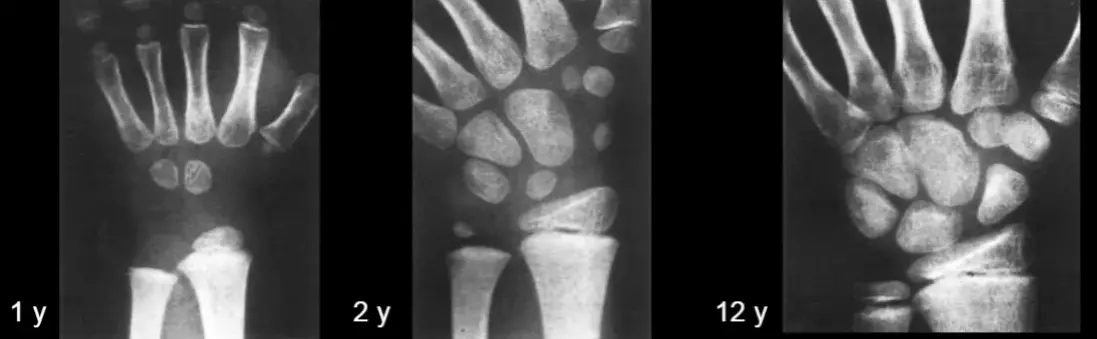

Ami igazán érdekes, az az, hogy születéskor ezek a csontok még puhák és rugalmasak. Később folyamatosan nőnek, erősödnek a különböző mozgások hatására. A tapintás, a fogás, a tárgyakkal való manipuláció mind ilyen. A csontok fejlődésén kívül az agyi folyamatokra is hatással vannak ezek a tevékenységek. A kéz finommozgásai az agyban történő idegimpulzusokkal összekapcsolódnak, és segítik a csecsemőket az objektumok érzékelésében. Lehetővé teszi számukra, hogy később finomabb mozgásokat végezzenek, például írjanak, rajzoljanak, kézműveskedjenek.

Fontos megjegyezni, hogy a csontok fejlődését genetikai adottságok is befolyásolják. Ezért eltérő a fejlődés üteme minden gyermeknél. Ez teljesen normális.

A kicsik 2 éves korban általában még mindkét kezüket egyformán használják. 3 éves kor után figyelhető meg, hogy az egyik kezet előnyben részesítik különböző tevékenységek során. 4-6 éves korban a domináns kéz egyre ügyesedik, majd 7 éves kor körül enyhe labilitás jellemző. A dominancia 8-9 éves korban stabilizálódik, de a kéz fejlődése majd csak 12 éves korban fejeződik be!

(A röntgen kép forrása: Általános csonttan és izülettan- Dr Kovács Magdolna Anatómiai Intézet 2007.02.12.)